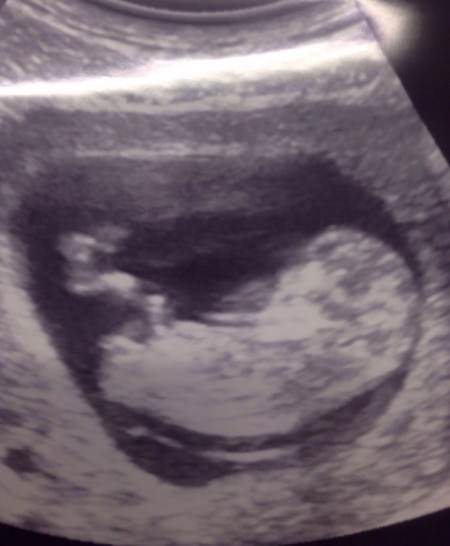

Hallo ihr Lieben, Ich war bei 11+2 am Freitag beim Arzt und Gott sei Dank ist auch bei uns alles super Das kleine hat sich total viel bewegt und meine Ärztin hat lange geschallt. Ich fragte Sie, ob man das Geschlecht schon erkennen könne. Sie sagte, allein aus rechtlichen Gründe dürfe sie es nicht sagen. Und zu diesem Zeitpunkt haben alle Kinder einen kleinen Zipfel an der Stelle. Allerdings sagte sie, wenn dieser eher waagerecht zur Wirbelsäule ist, dann ist die Wahrscheinlich groß, dass es ein Mädchen wird. Bei mehr als 30 grad nach oben eher ein Junge. Ich habe meine Schwester mal nach ihren Ulraschallbildern aus der Zeit befragt und es stimmte (sie hat 2 Söhne) Was haltet ihr davon? Ich hab mal ein Bild angegangen. Vielleicht können wir ja vergleichen und in ein paar Wochen mal schauen, ob es stimmt ;) Sonnige Grüße an alle, Quenn.

Bild zu Geschlecht schon in der 12 SSW erkennen? - Forum für März - Mamis

Hallo, tolles Bild! Ist das diese NUB Theroie ? Die ich eh nie verstehe Also meine beiden Mädchen die ich hier habe erkannte man immer sogar in der 18ssw noch als Junge. Meine erste outete sich in der 32 ssw und meine kleine war dann bei dem großen Degum 2 Schall in der 22 ssw ein Mädchen. Vorher waren das immer Jungs. Das wäre ja schon recht männlich von dem keinen Kerl Finds aber noch zu früh um es zu glauben, mag fälle geben jedoch wäre dich dem nicht so aufgeschlossen. Was sagt Dein Bauch Dir, was hast du gedacht als du Dir Gedanken gemacht hast, über das Geschlecht?

irgendwie würde ich mich über einen Jungen mehr freuen. Aber wenn ich erfahre, dass es ein Mädel wird, werd ich sicher keine Minute brauchen, um mich "umzustellen". Ich hatte halt von Anfang an so ein Gefühl... Diese NUB Theorie ist allerdings tatsächlich ziemlich interessant. Einige Frauenärzte prognostizieren auch ab der 12. SSW damit. Danach sieht es bei mir eher nach einem Mädel aus. So wie ich das im Netz mitbekommen habe, ist das in UK total verbreitet. Würde mich mal interessieren, ob erfahrene Mamas hier damit Erfahrungen haben und welche...

J oder M ? Bitte um Vorschläge